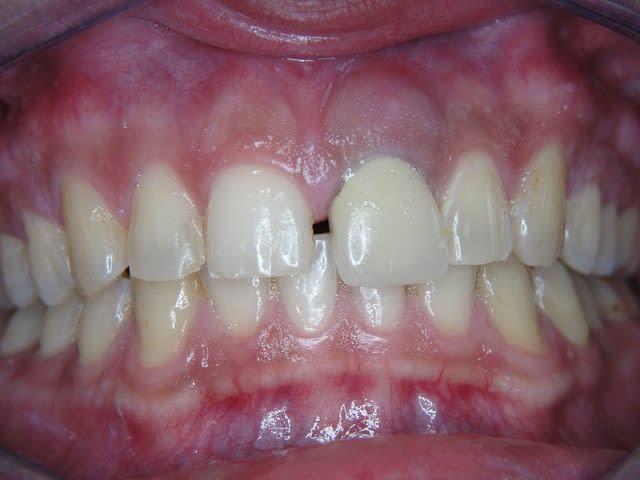

J'ai de tout en boutique..jeune homme 25 ans accident de piscine choc sur la bordure ( fêlure existante..fistule), extraction le jour même, temporisation 4 mois (avec un bout de trombone) Monobloc 16mm 60N, prep cap zircone droit 2/2 provisoire ion, temporisation 3 mois ceramo ceram..

J'ai de tout en boutique..jeune homme 25 ans accident de piscine choc sur la bordure ( fêlure existante..fistule), extraction le jour même, temporisation 4 mois (avec un bout de trombone) Monobloc 16mm 60N, prep cap zircone droit 2/2 provisoire ion, temporisation 3 mois ceramo ceram.. suite des photos :)